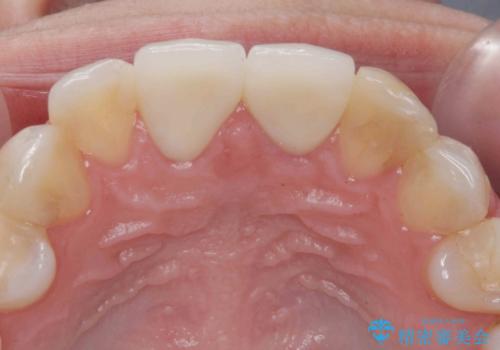

両側の前歯に根尖性歯周炎を認めたため根管治療を行ったのち、ジルコニアクラウンを用いた審美性の改善を計画します。

前歯の見た目が改善したことで長年の悩みが解決できた。と治療内容に満足いただくことができました。